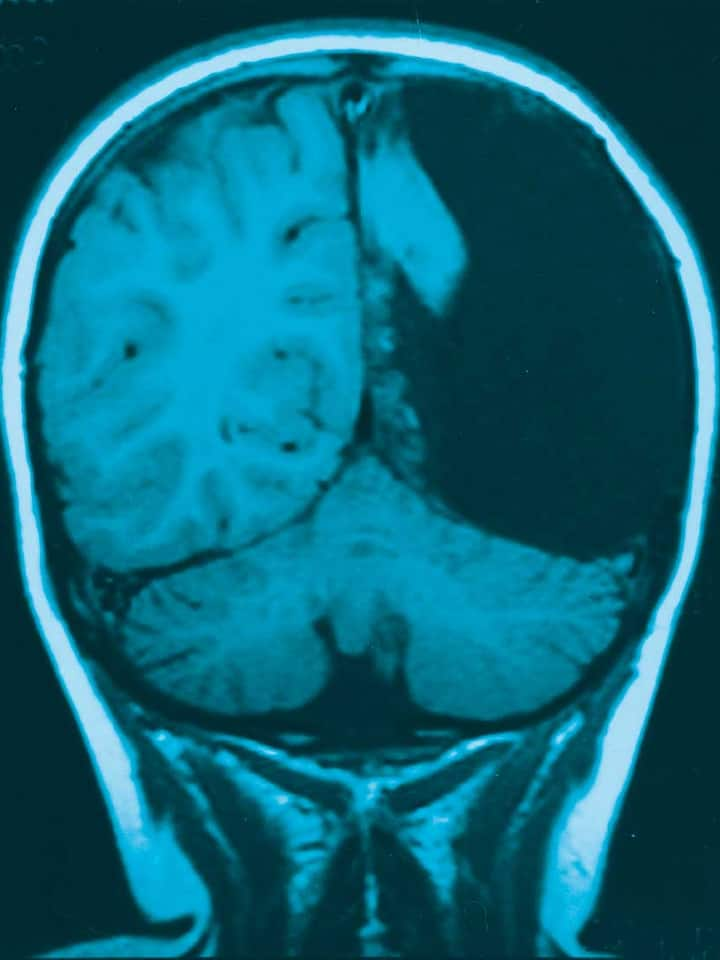

Auch Arno Villringer kennt solche Fälle aus der klinischen Praxis. «Ich erinnere mich an einen Patienten, der sich untersuchen liess, weil er Kopfschmerzen hatte oder etwas in dieser Art», sagt der Direktor der Abteilung Neurologie am Max-Planck-Institut für Kognitions- und Neurowissenschaften in Leipzig. «Als ich sein Computertomografiebild sah, war gleich klar, dass er fast kein Gehirn hatte. Ein unglaublich grosser Hydrozephalus und nur ganz schmale Streifen Hirnrinde. Der Mann lebte ein unauffälliges Leben, das war eine Zufallsentdeckung.» Villringers Folgerung: «Offensichtlich kann man mit vergleichsweise wenig Gehirn schon sehr viel leisten.»